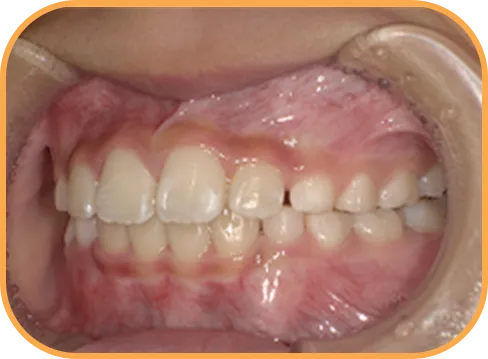

• After

• 正 面

治療後正面からの歯の様子

• 上 顎

治療後上顎からの歯の様子

• 下 顎

治療後下顎からの歯の様子

• 右 側

治療後右側からの歯の様子

• 左 側

治療後左側からの歯の様子

主 訴

前歯ガタガタ、前歯が大きい

治療内容

インビザライン・ファースト

治療期間

7か月

治療費(税別)

450,000円+診断料5,000円

リスク・副作用

• 親知らずの影響や加齢などによって、凸凹が生じる可能性があります。

• 治療の初期段階では痛みや不快感が生じやすくなりますが、1週間前後で慣れます。

• 顎の成長発育によって、噛み合わせや歯並びが変化する可能性があります。

• 状況により当初予定した治療計画を変更する可能性があります。